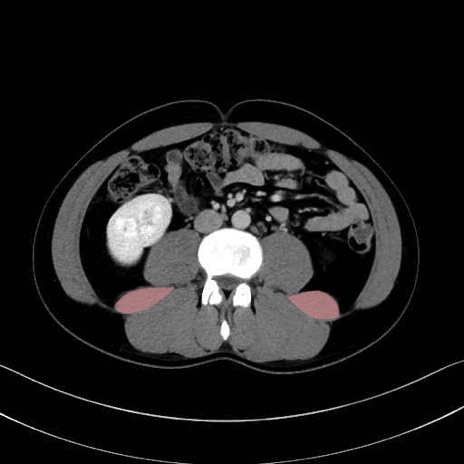

腰方形筋 (Quadratus lumborum)

大腰筋 (Psoas major)